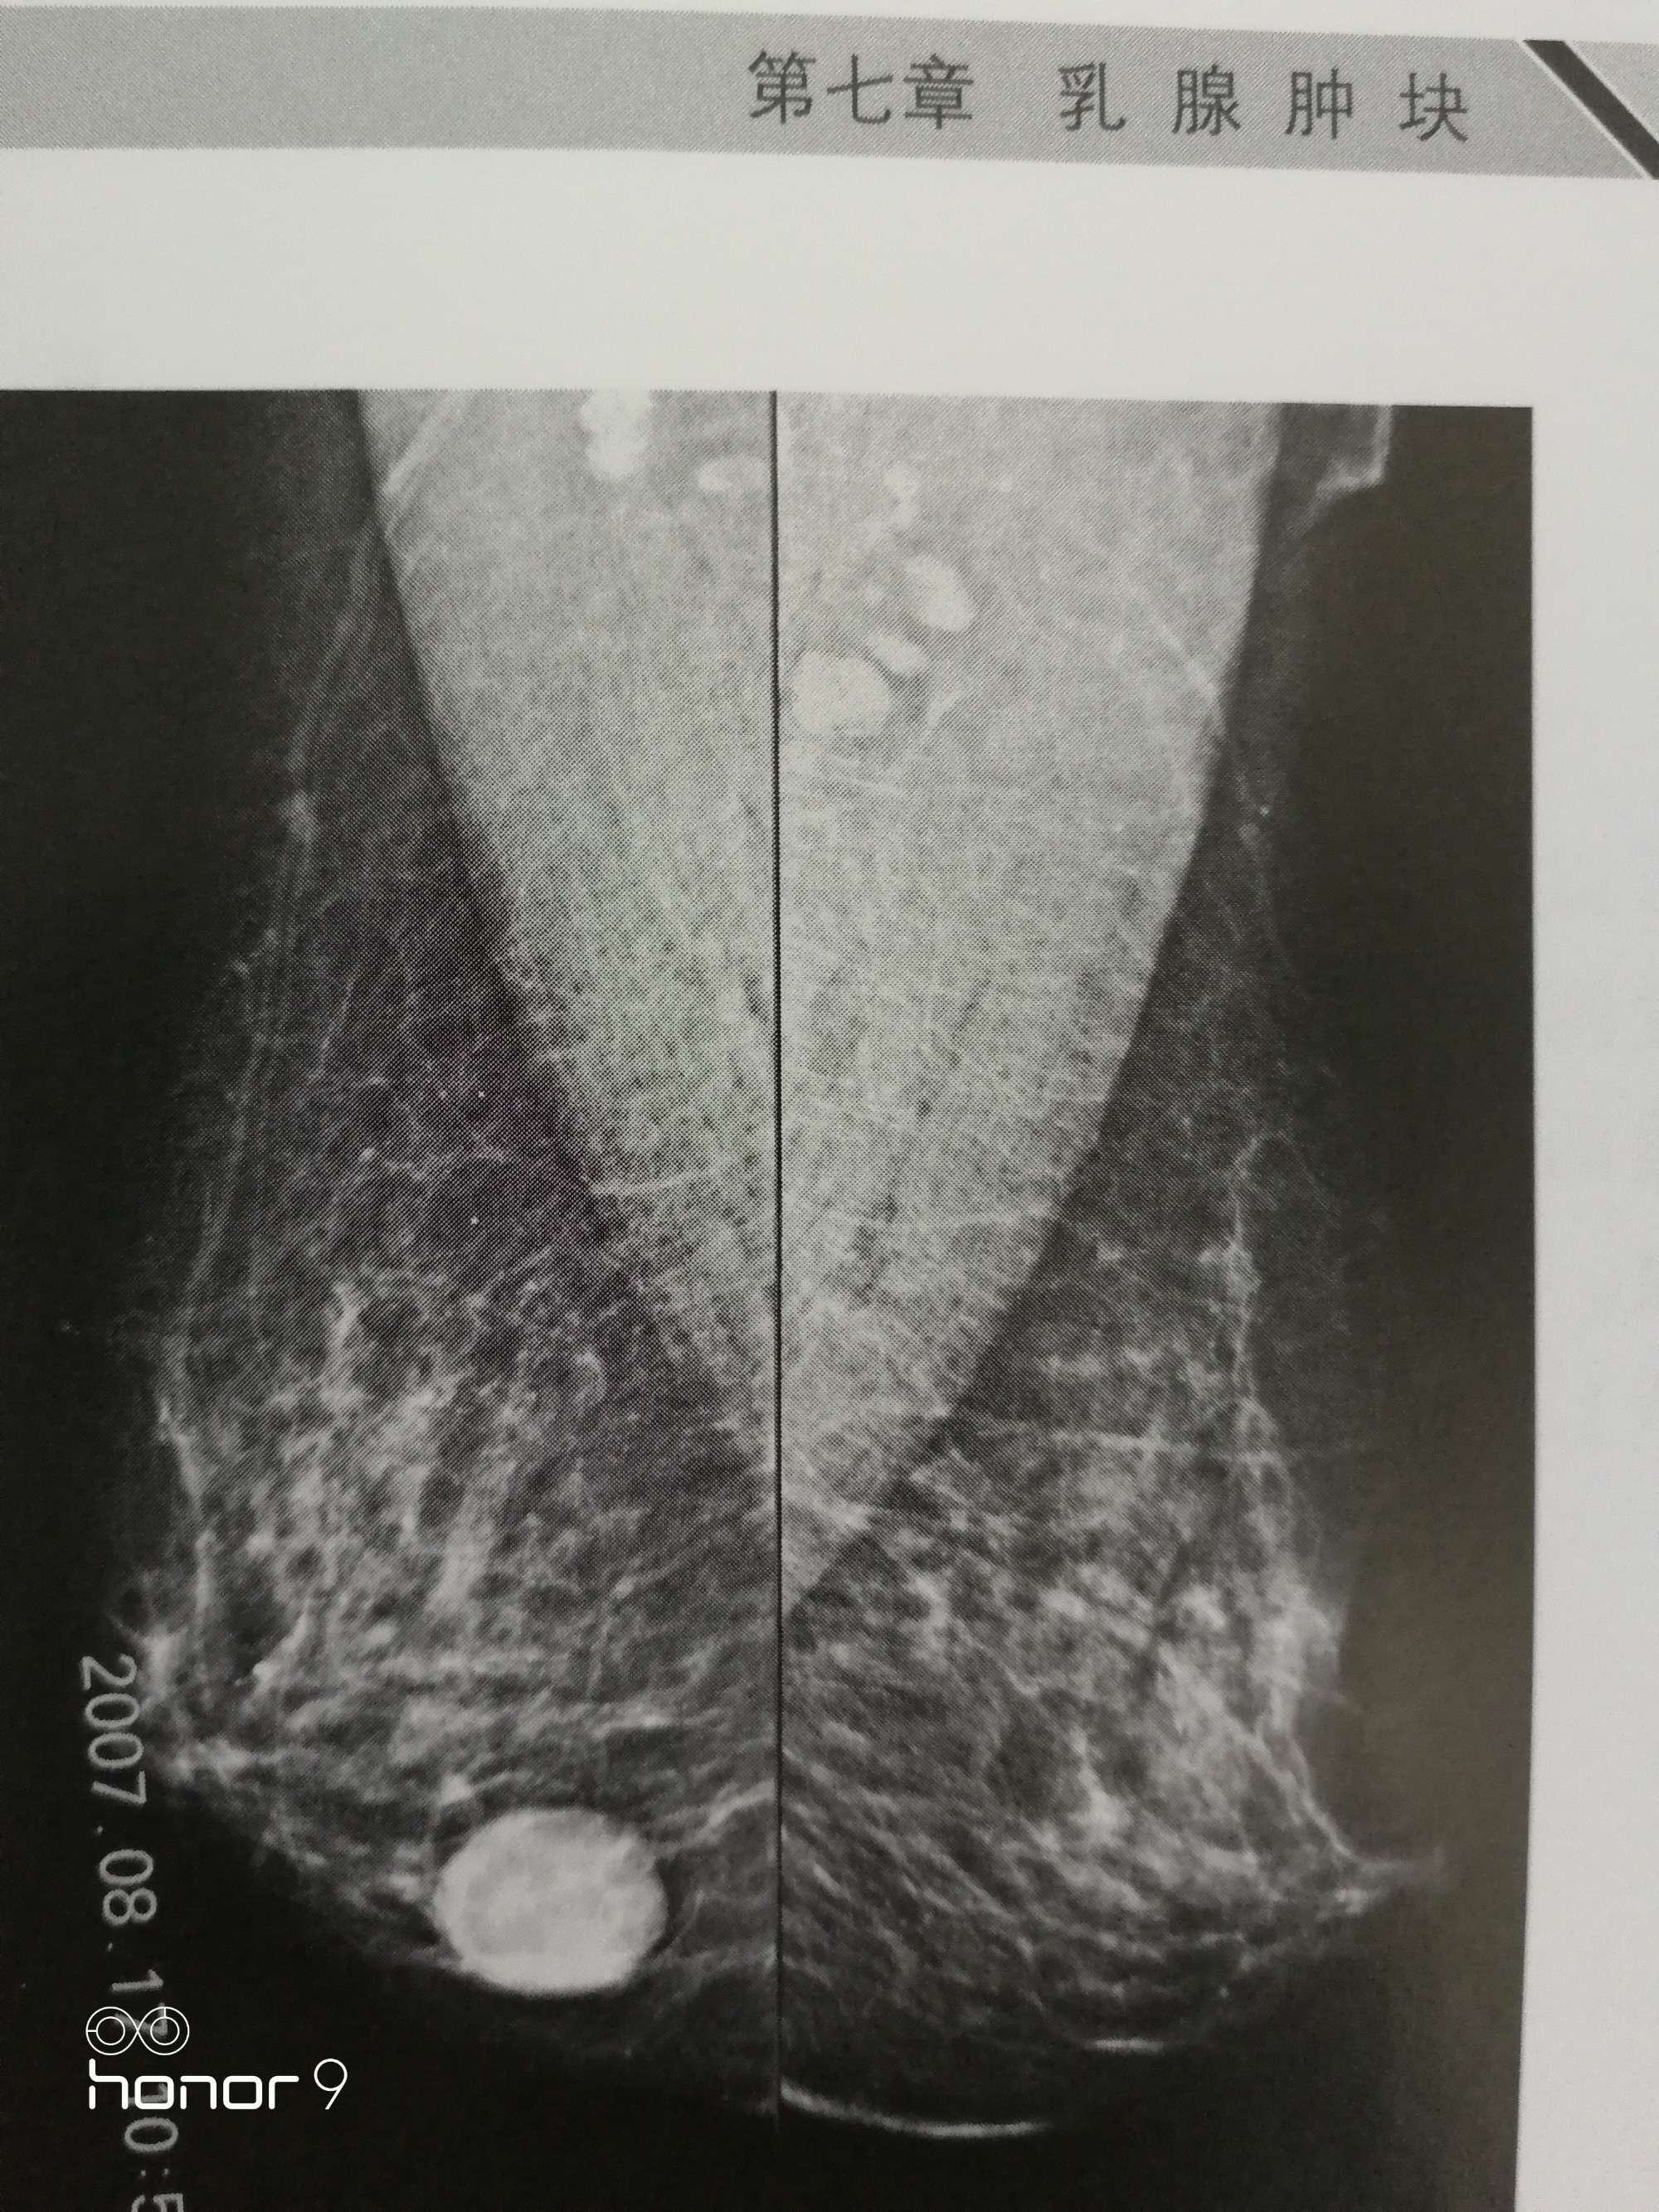

第二:乳腺纤维瘤一般单发,呈圆形或椭圆形,表面光滑,边界清楚,可以推动,与皮肤和深部组织不粘连,腋窝淋巴结也不肿大。它一般生长较缓慢,不痛或仅有轻微的胀痛、钝痛,患者平时可能没有什么感觉。由于患乳腺纤维瘤之后的疼痛和月经周期没有关系,因此很容易和乳腺增生区别开来。